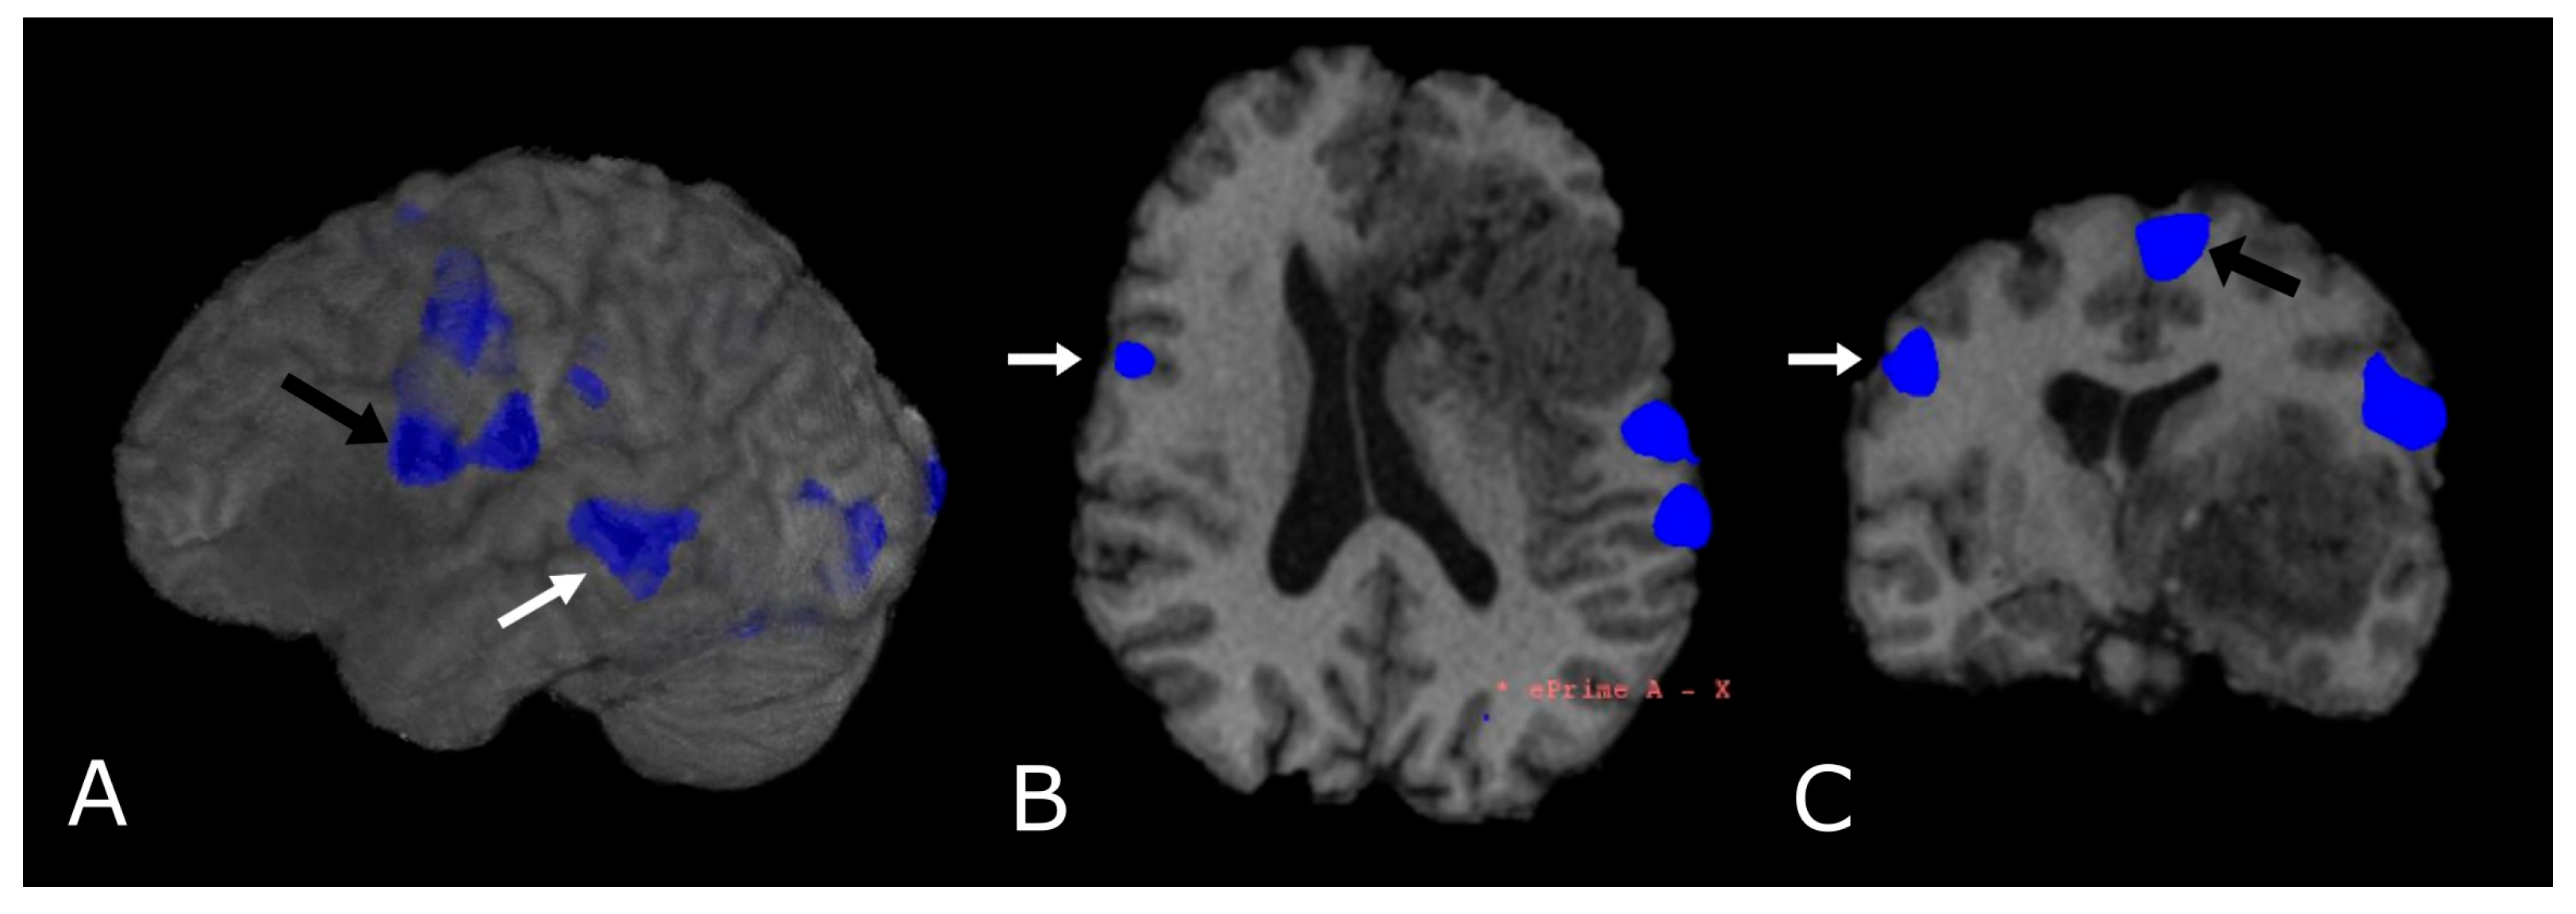

Most fMRI clinical exams are task-based, so that the subject is asked to perform an action in response to a stimulus aimed at the activation of a specific cortical area, alternated with control/rest phases. Alterations of the BOLD signal are then analyzed to localize the area under consideration (Figure 12). Task-based fMRI has proven to be a valid and highly sensitive tool for localizing the distinct eloquent cortical and subcortical areas before surgery in glioma patients, also showing good accuracy when compared to intraoperative stimulation mapping data. Task-based fMRI is reported to be more accurate in LGGs than in HGGs, due to neurovascular uncoupling [118,119,120], the presence of arteriovenous shunting, mechanical vasoconstriction caused by tumoral mass effect, and the presence of intratumoral hemorrhages.

Figure 12.

Language task-based fMRI. fMRI correlation maps of cortical activation during language tasks in a patient with frontal-temporal-insular GB. Blue represents areas of increased cortical activation. (A) 3D surface rendering with BOLD signal overlay reveals the activation of Broca’s Area, displaced posteriorly by the lesion (black arrow; expressive speech) and in the superior temporal gyrus (white arrow, Wernike’s Area, receptive speech); (B,C) Axial and coronal deskulled T1w-BRAVO with BOLD signal overlay confirm the activation and the dislocation of Broca’s Area and shows a significant but smaller activation in the right inferior frontal gyrus (white arrow’s head). Black arrow’s head indicates the supplementary Motor Area (C).

To date, the use of fMRI is targeted towards pre-surgical planning and identification of eloquent areas (language [112,113], motor [114], vision and memory areas [115]) adjacent to the tumor, where the need for an extensive resection must be counterbalanced by the sparing of functional cortical and subcortical structures. The assessment of lesion-to-activation distance has been considered relevant for the evaluation of postoperative outcomes. In general, it is assumed that the risk of postoperative loss of function, assessed with fMRI, is significantly lower when the distance between tumor periphery and BOLD activity is at least 10 mm [116,117].